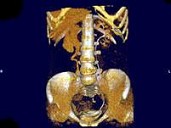

- 多项选择题女,44岁, 突发性胁腹部绞痛并向会阴部放射伴血尿一次,CT扫描如图所示, 下列说法正确的是 ( )

A、右侧肾盂肾盏扩张

B、右输尿管中上段扩张

C、右输尿管内可见沿输尿管走行的高密度影

D、右输尿管结石

E、左肾输尿管未见异常